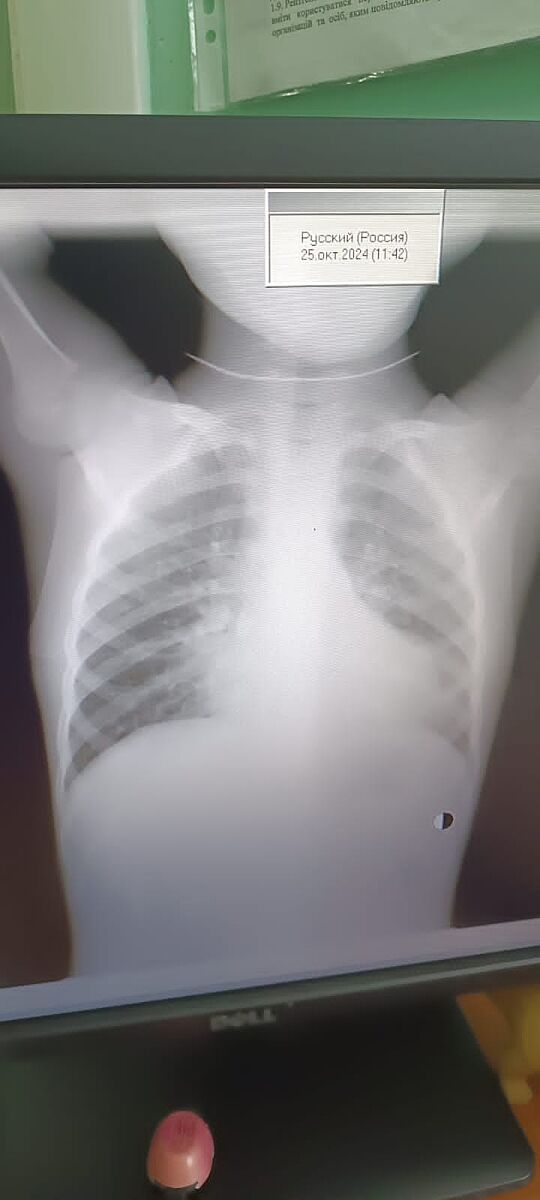

Дитині сьогодні зробили рентген,але розшифрують в понеділок. Можливо тут є лікарі, які зможуть сказати чи є запалення? Дякую.

Потому что даже два ваших фото сильно отличаются

Сложно сказать, снимок экрана не качественный. Вроде нет, смущает только один участок, но там размыто

Педіатр, на відміну від нас, бачить клініку і має дані огляду.

Ще додам. Можливо, педіатр саме в тій ділянці, що мені не подобається, чула ослаблене дихання, і тоді так, для неї це не просто неякісний знімок, вона побачила підтвердження